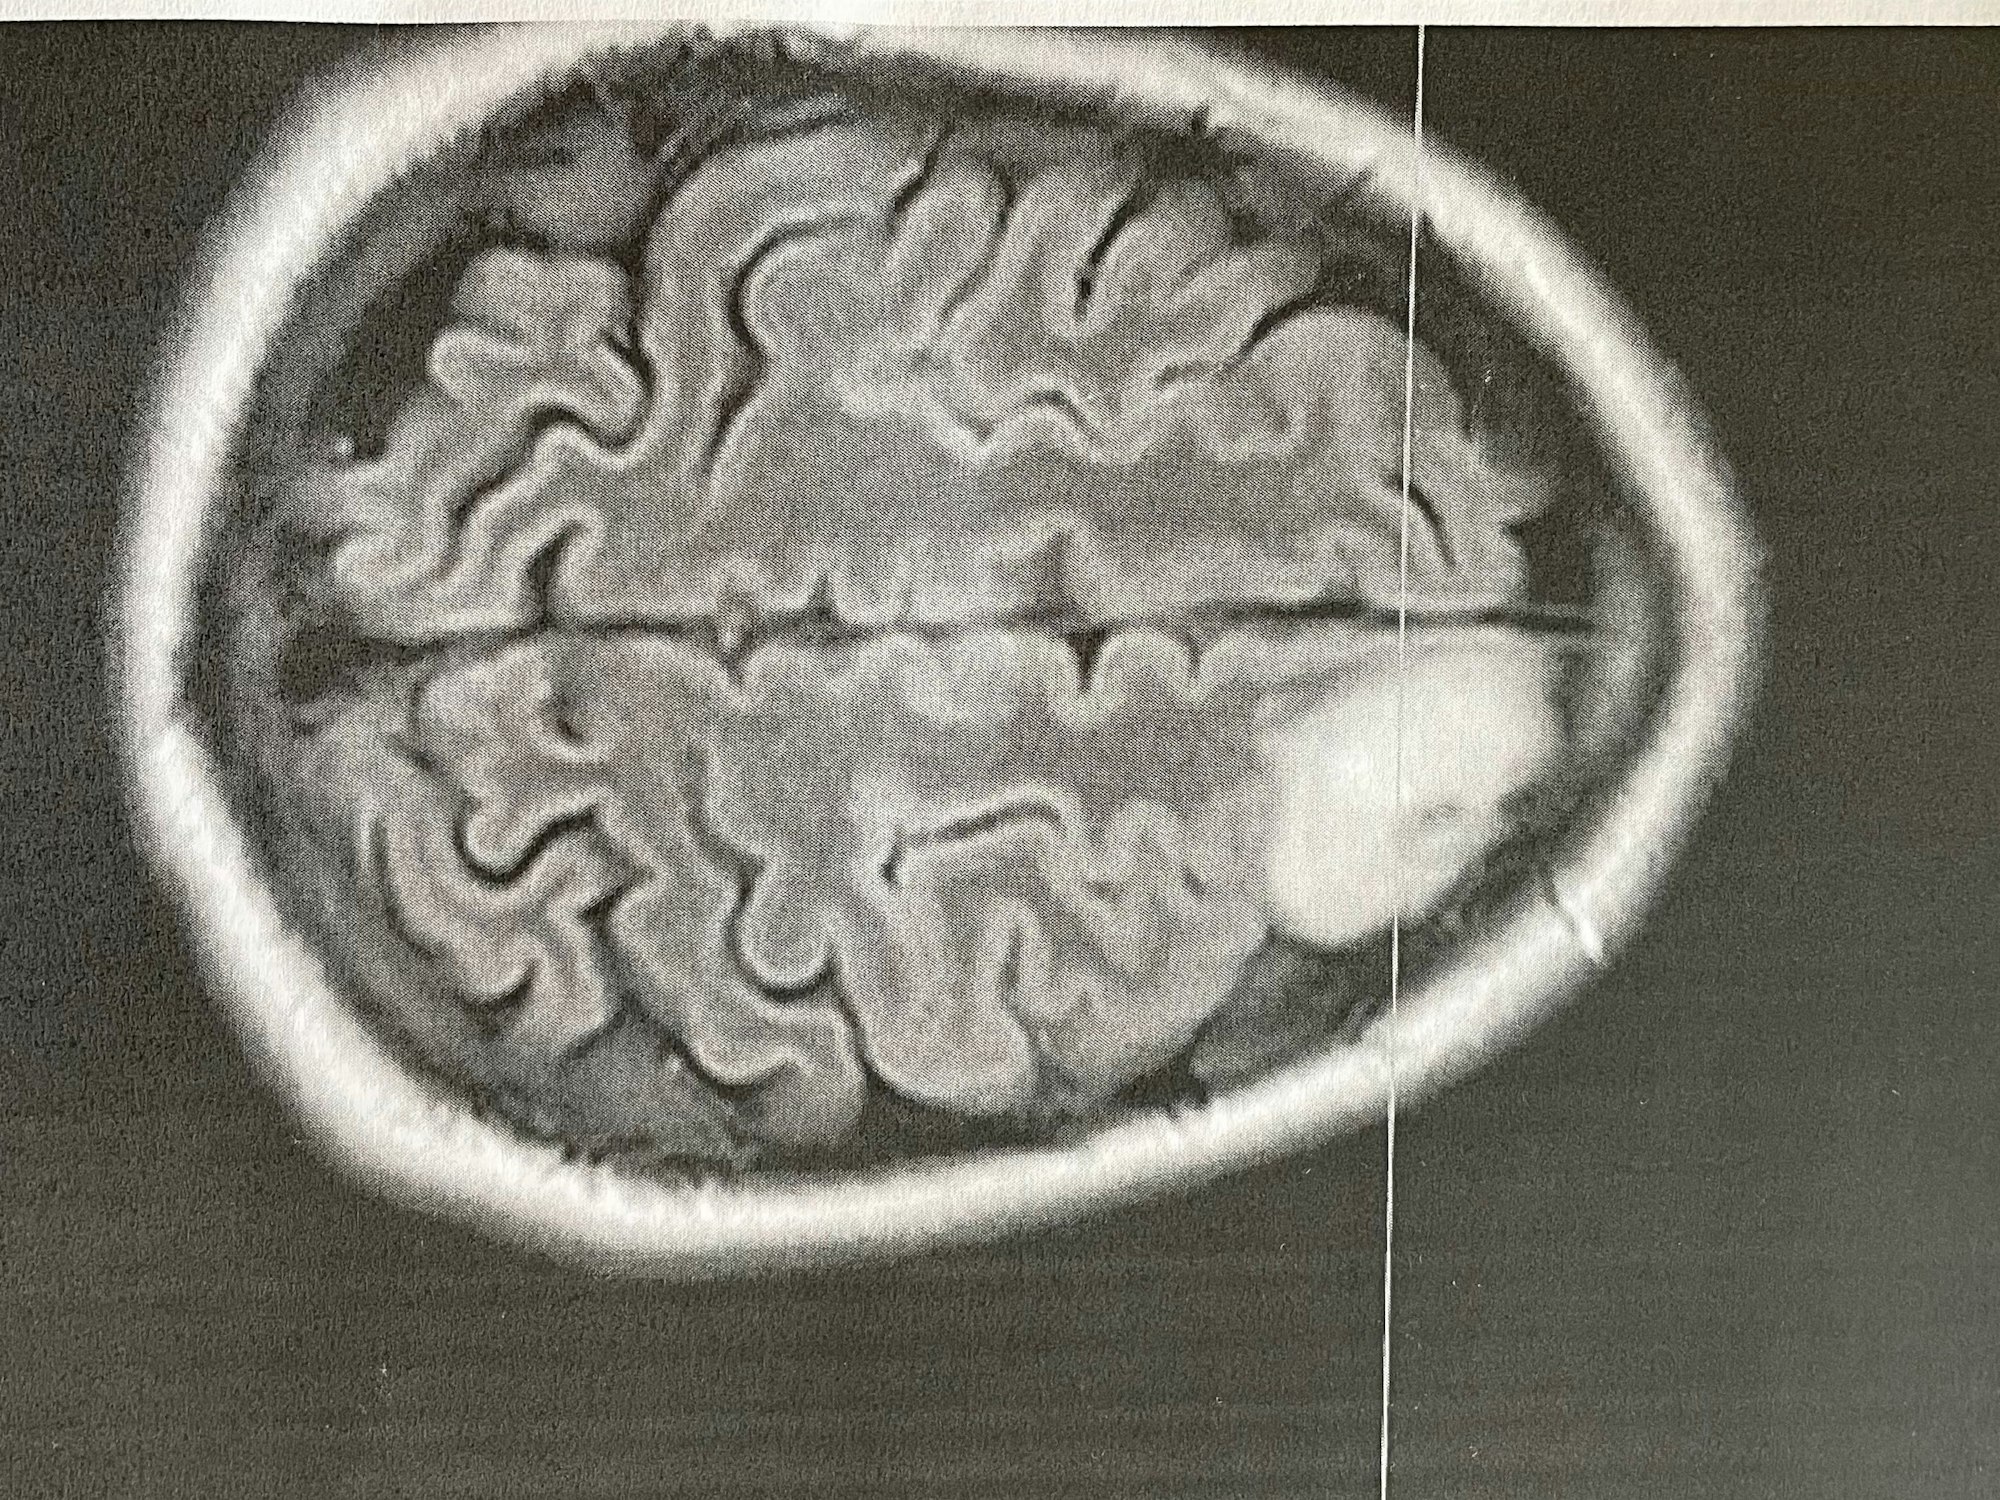

Eine Querschnittsaufnahme des Gehirns zeigt den mandarinengroßen Tumor (rechts, weiß)

An die Tage vor der Operation erinnert er sich sehr gut. In der Nacht zum 12. April habe er die Kontrolle über seinen Körper verloren, ahnte aber nicht, dass es ein epileptischer Anfall war. Er habe später rote Striemen am Rücken entdeckt und auf eine Gürtelrose getippt, verbunden mit einem schweren Magen-Darm-Infekt. Im Taxi zum Krankenhaus der zweite Krampfanfall – „jetzt war klar, dass es etwas Neurologisches ist.“ CT und MRT bringen die Gewissheit: ein Tumor. „Gut zu operieren, weil im Frontallappen“, habe es geheißen, und: „Zu 90 Prozent gutartig.“ 90 Prozent, wieder so eine dumme Zahl. Für den Arsch.